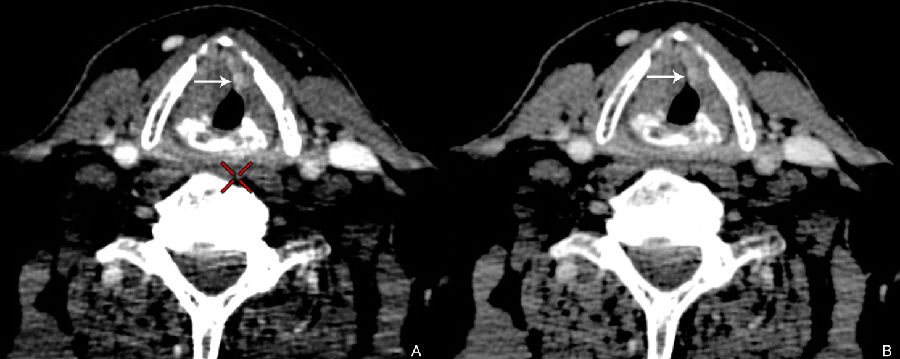

图2:57岁男性,喉癌患者,单能图像较混合能量图像更清晰显示较小病变(左图为常规混合能量图像)